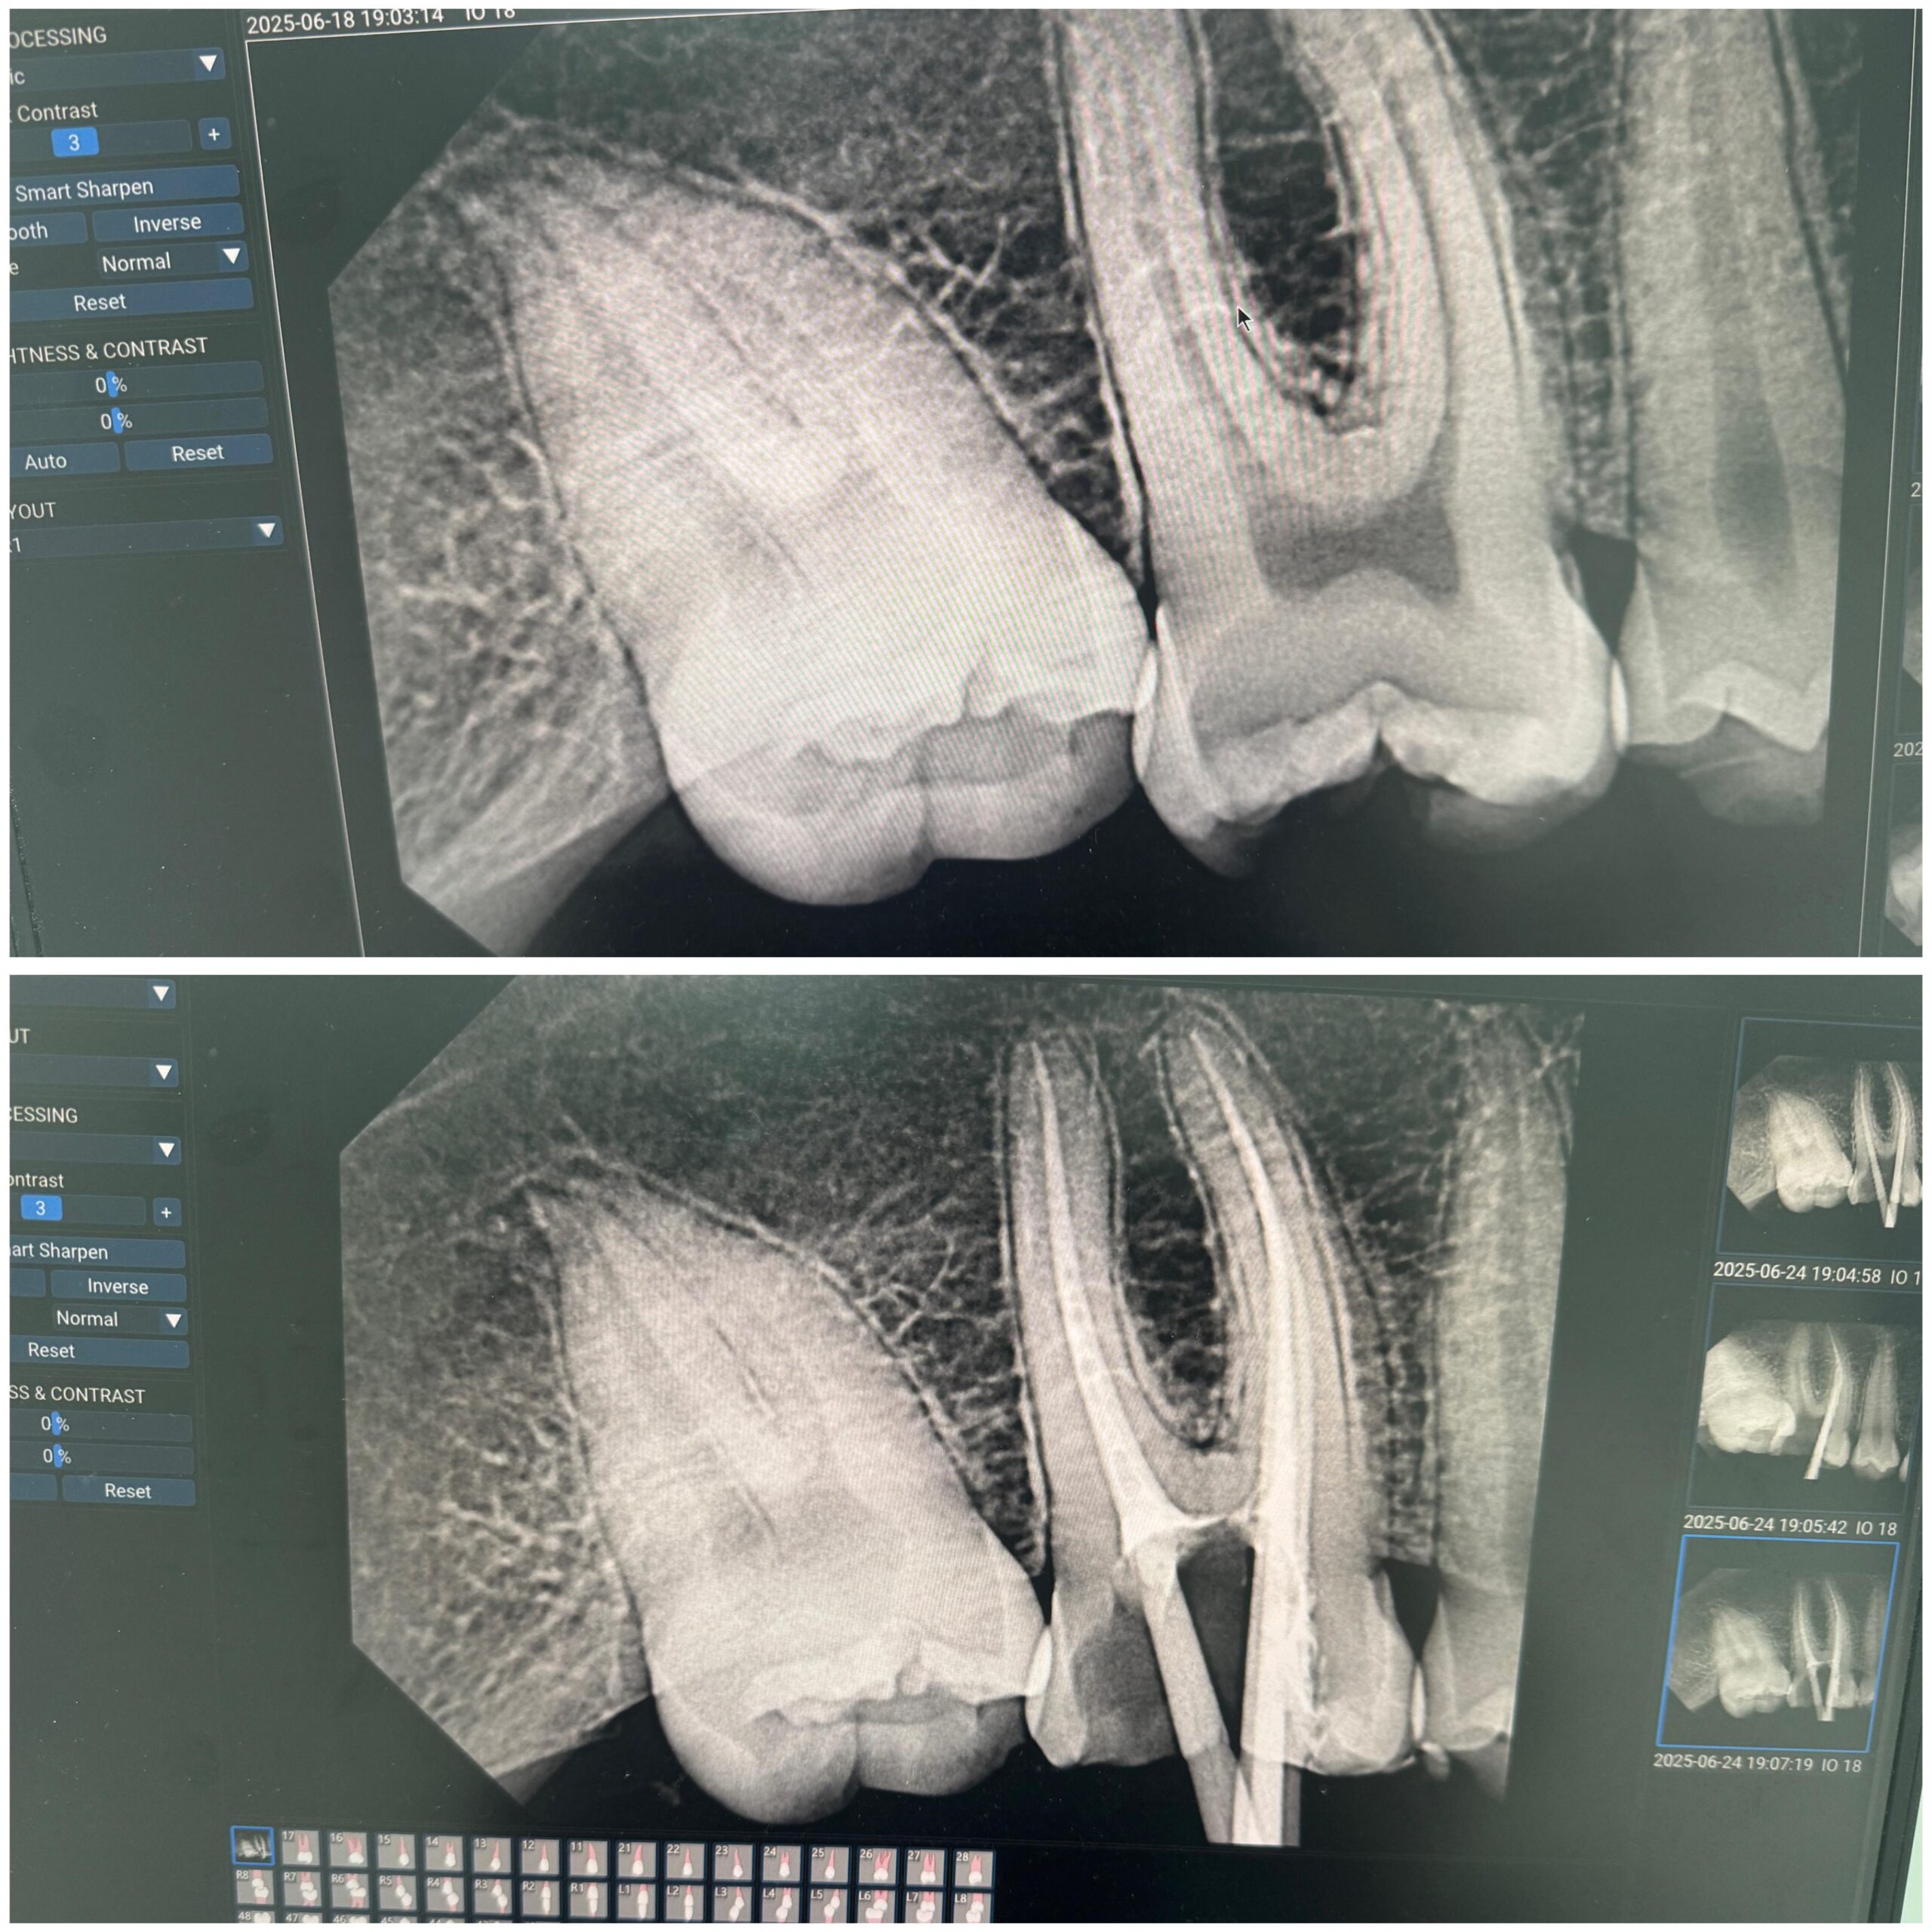

• Accurate diagnosis of nerve condition using the latest radiology equipment.

• Using modern root canal filling devices to ensure accurate and efficient cleaning of the nerve canals.

• Extensive experience in treating complex cases such as chronic nerve inflammation or tortuous canals.

A filling, or mata, for chronic dental treatment is a medical procedure that aims to reduce the size of a tooth affected by decay or inflammation of the pulp (dental pulp), rather than requiring extraction. This treatment involves removing the affected tooth and its multiple trigeminal roots, carefully assessing them, then filling them with a special medical material for infection. Finally, the tooth is generally restored to its normal shape and appearance.

A root canal filling is typically performed when decay has penetrated the deep layers of the tooth, or when a fracture has occurred that exposes the nerve. Thanks to modern technologies, this procedure is now painless and delivers long-lasting results, especially when performed under the supervision of a specialist like Dr. Ahmed Essam, who combines international experience with a commitment to patient comfort in an advanced treatment environment.